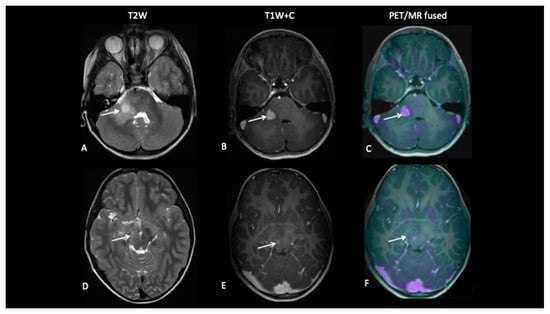

A 10-year-old presented with low-grade glioma with a background of NF1 (neurofibromatosis type 1). A mid treatment MRI scan following disease progression showed enlargement of an enhancing lesion in the right cerebellar hemisphere, but the patient was well and clinically stable, and the radiological changes were thought to reflect pseudoprogression. An FDOPA PET–MRI showed increased tracer activity in the enhancing lesion along with a second FDOPA avid lesion in the right subthalamic region, consistent with metabolically active disease (Figure 9).

Figure 9.

A mid-treatment scan demonstrates an enlarging right cerebellar hemisphere lesion (A,B) thought to reflect pseudoprogression, but FDOPA demonstrates increased uptake (C) and identifies a further lesion in the midbrain (F) not obviously apparent on the T2W image (D) or T1W post-contrast image (E), which is consistent with multifocal tumour progression.